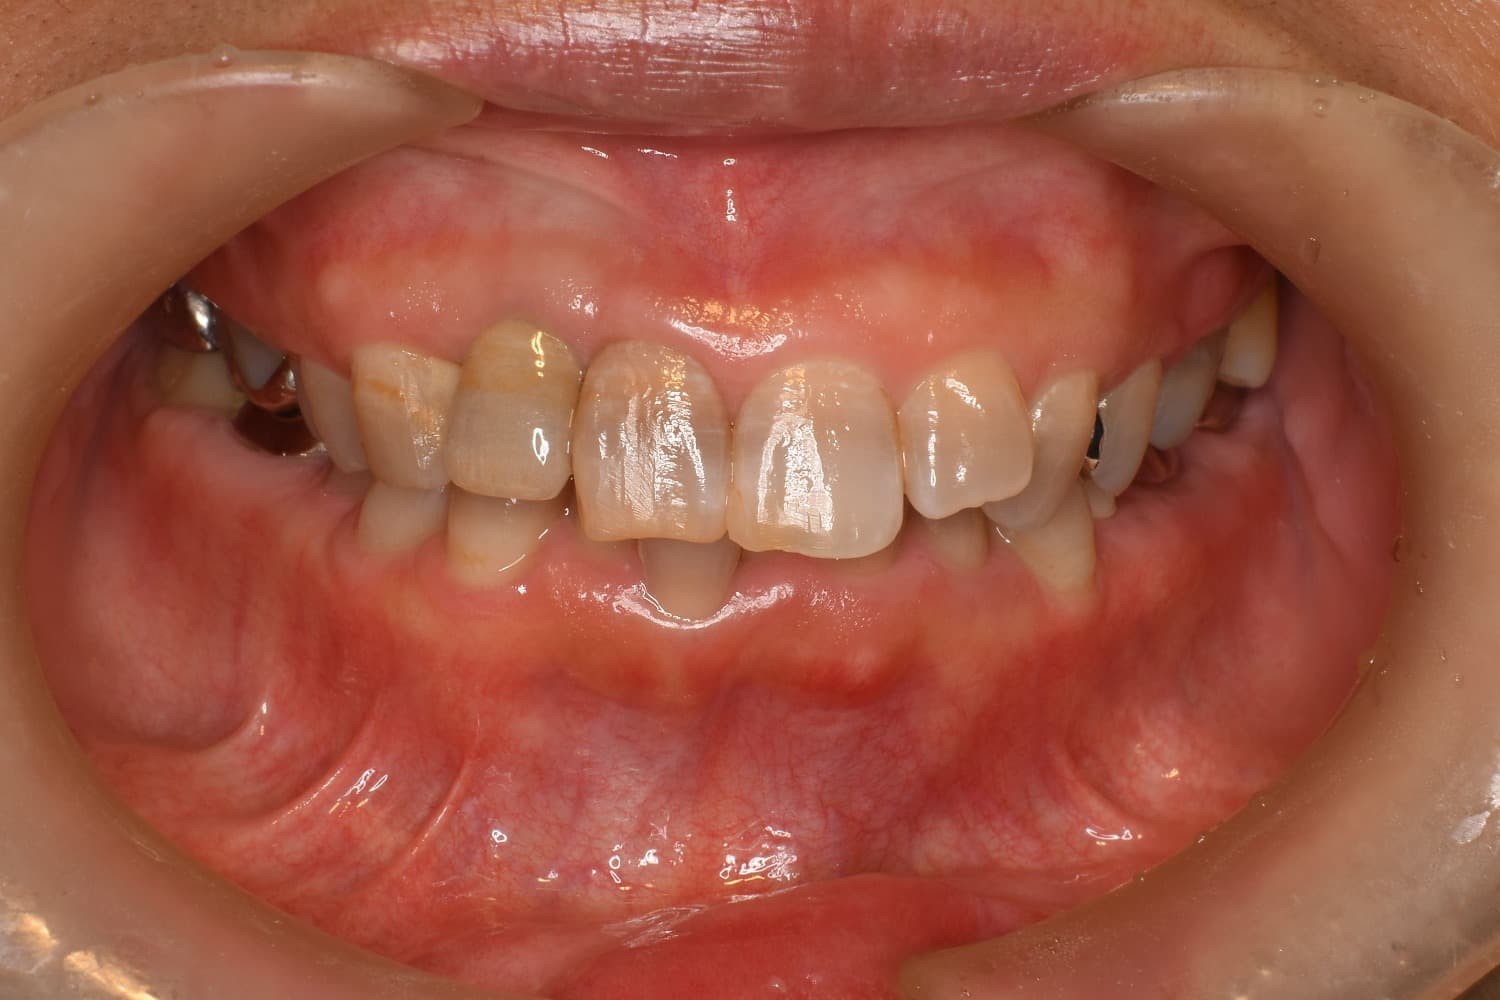

右上前歯のインプラント治療(40代女性)

Before

After

右上2番目の歯が縦に割れていたので抜歯をして、インプラントによる治療をおこなう。

年齢

40代

性別

女性

主訴

3日前から右上の前歯がズーンと重く痛い。

治療期間

約6ヵ月

治療回数

8回

費用

510,000円(税込み561,000円)

副作用・リスク

・治療後のメンテナンスが必要 ・清掃不良によるインプラント周囲炎 ・咬合力の強さによる被せ物の脱離や破損